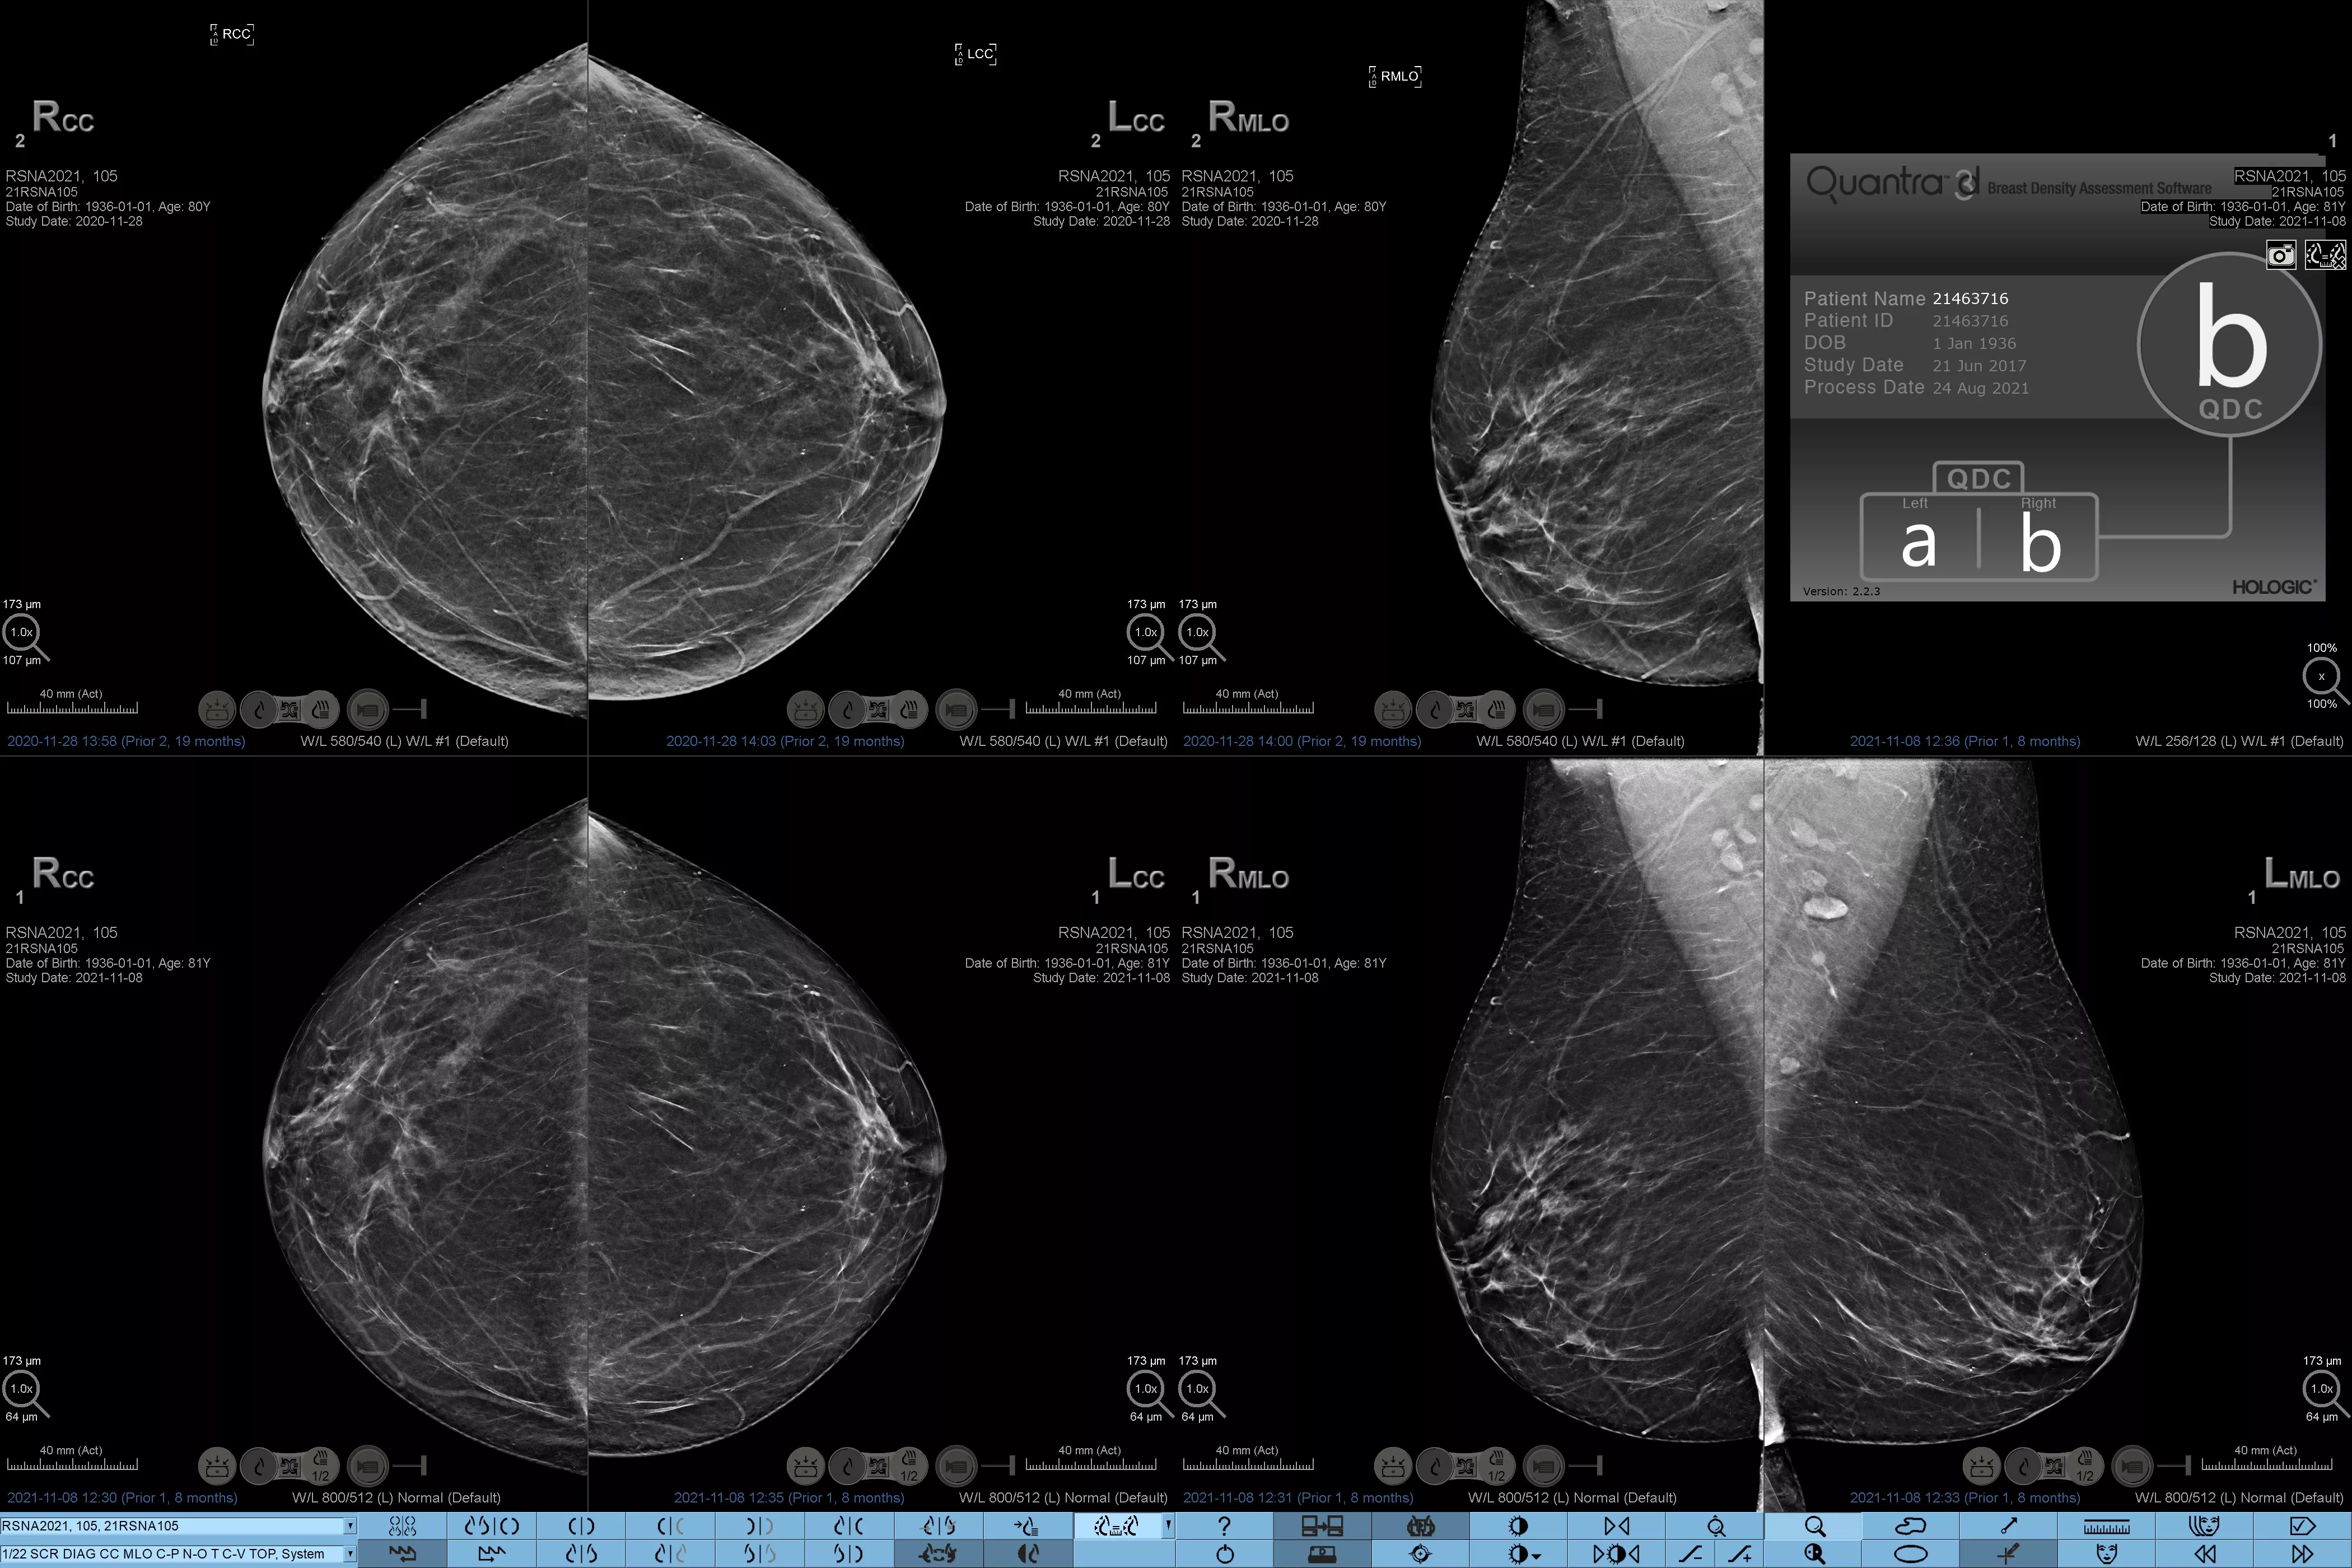

Higher breast density is known to increase a woman’s risk for breast cancer.1 The need for accurate, unbiased analysis is therefore critical. Powered by machine learning, Quantra technology software analyses both 2D™ and tomosynthesis images for distribution and texture of parenchymal tissue. It categorises breasts in four breast composition categories consistent with guidance from the American College of Radiology (ACR) BI-RADS Atlas 5th Edition.2

8. Breast composition categories as described in ACR BI-RADS Atlas.